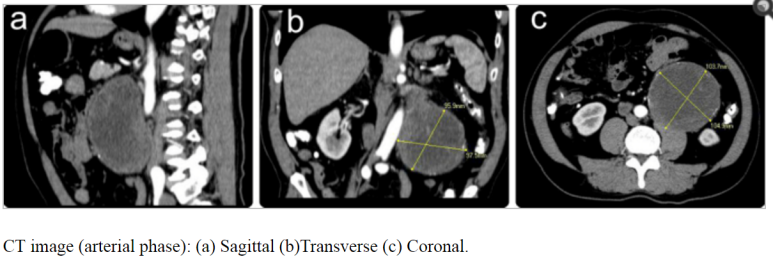

화살표는 대동맥

5.6 cm 낭성 종양 직 상부로 상장간막 동맥, 정맥이 위치하고 있다. (파란 별 아래 위치)

anterior pararenal space에 위치하는 것으로 생각된다.

대학병원에서 CT시행 판독

; r/o lymphangioma, neurogenic tumor with cystic change, mucinous cystadenoma